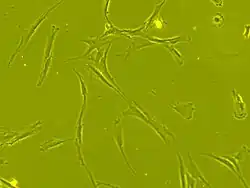

Human bone marrow-derived Mesenchymal stem cell showing fibroblast-like morphology seen under phase contrast microscope (Carl Zeiss Axiovert 40 CFL) at 63 x magnification

An example of human mesenchymal stem cells imaged with a live cell imaging microscope

The cell body contains a large, round nucleus with a prominent nucleolus, which is surrounded by finely dispersed chromatin particles, giving the nucleus a clear appearance. The remainder of the cell body contains a small amount of Golgi apparatus, rough endoplasmic reticulum, mitochondria, and polyribosomes. The cells, which are long and thin, are widely dispersed, and the adjacent extracellular matrix is populated by a few reticular fibrils, but is devoid of the other types of collagen fibrils.[13][14] These distinctive morphological features of mesenchymal stem cells can be visualized label-free using live cell imaging.